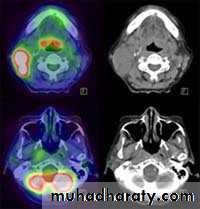

Positron emission tomography (PET) and PET-CT

• PET is an established imaging technique, most commonly used in oncology.• The most commonly used radiopharmaceutical in PET scanning is FDG (2-deoxyglucose labelled with the positron-emitter fluorine-18).

• The current roles of PET imaging may be summarized as follows:

• Oncology:

• Tumor staging.

• Assessment of tumor response to therapy.

• Differentiate benign and malignant masses, e.g. solitary pulmonary nodule.

• Detect tumor recurrence.

• Cardiac: Non-invasive assessment of myocardial viability

in patients with coronary artery disease.

• Central nervous system:

• Characterization of dementia disorders.

• Localization of seizure focus in epilepsy.